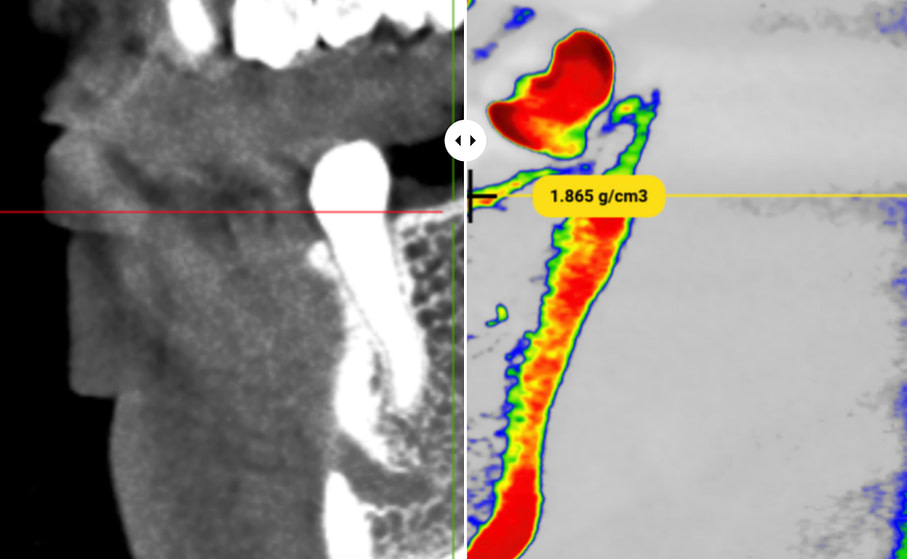

SimDensity - AI-Powered Bone Density Analysis

Visual Tech-lab showcased their SimDensity platform at IDS 2025, offering a AI-powered bone density measurement technology using existing CBCT data with a proprietary bone density phantom standard.

The technology analyzes CBCT scans to provide quantitative bone density measurements particularly valuable for pre-operative implant planning. Beyond implantology, SimDensity offers applications in orthodontic treatment planning for both clear aligner and traditional bracket systems, helping identify potential limitations or considerations related to bone density before initiating tooth movement.

What makes the system particularly practical is its seamless integration with existing CBCT technology without requiring additional patient radiation exposure. The cloud-based platform approach allows for implementation without significant hardware investments or workflow disruptions.

SimDensity represents another example of how artificial intelligence is extracting more clinical value from existing diagnostic imaging, providing quantitative data points that enhance evidence-based treatment decisions and potentially improve predictability of outcomes.